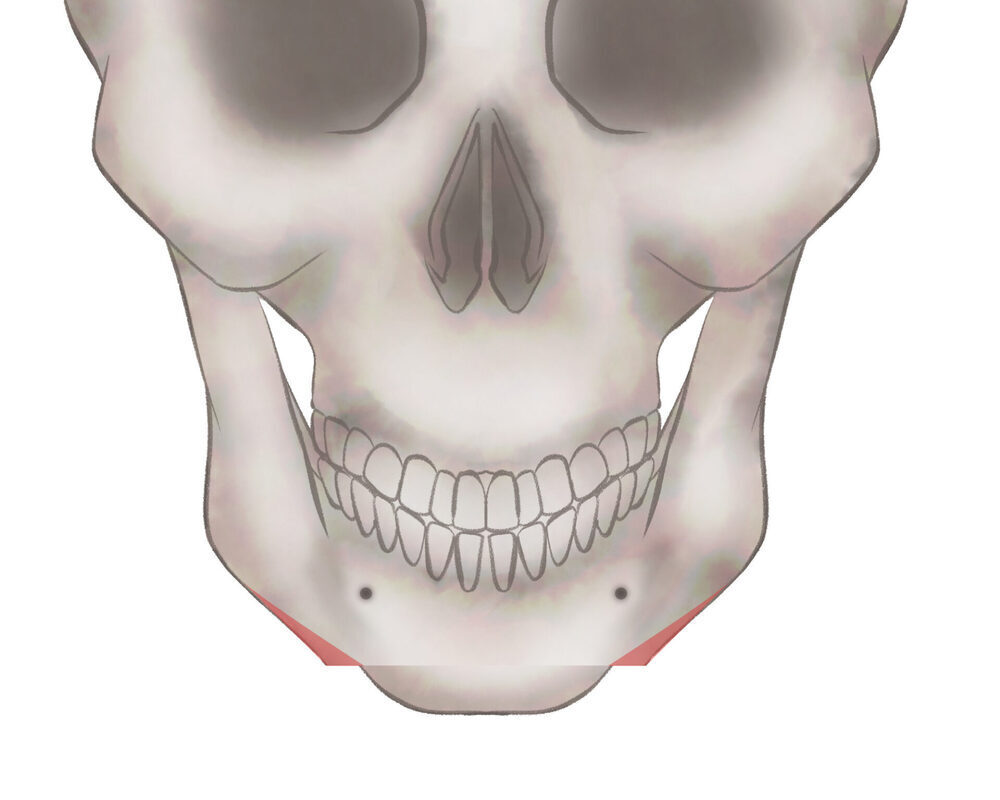

オトガイT字骨切り(Vライン形成)

1.切開線をデザインします

2.骨を切り離す、もしくは取り除きます

3.骨を移動させ段差を削ります

4.プレートで固定します